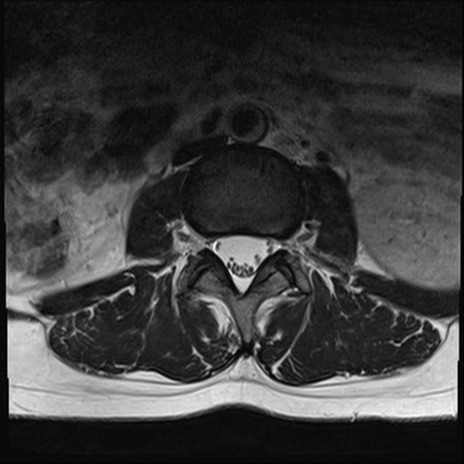

【整形】TIPS症例4 腰椎MRI T2WI(横断像)

横断像と矢状断像